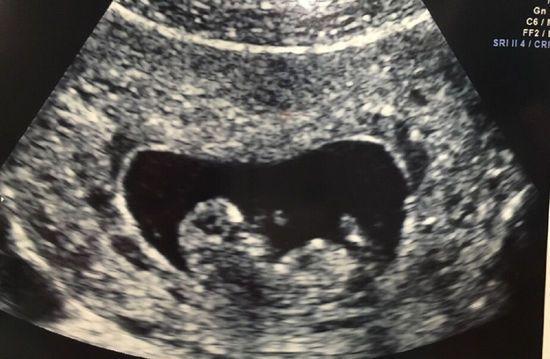

- 检查子宫形态: 确认子宫是否正常,有无畸形(如纵隔子宫、双角子宫等)、子宫肌瘤、子宫腺肌症等问题,这些问题可能会影响受精卵着床或导致流产。

- 检查卵巢储备功能: 通过B超可以清晰地看到卵巢内卵泡的数量和大小,评估卵巢的储备功能,这对于预测生育能力非常有帮助。

- 排查卵巢囊肿或肿瘤: 及时发现卵巢上的囊肿、肿瘤等异常,并进行相应处理。